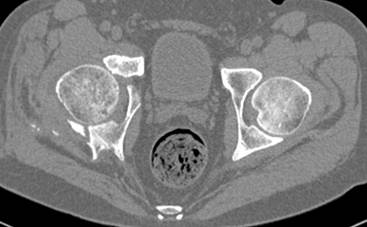

Интересно было бы посмотреть рентгенограммы до операции. У меня впечатление, что я не все вижу, что тут есть... Уважаемые Господа "тазисты" и "тазологи", к какому типу переломов вертлужной впадины по Летурнелю вы бы отнесли это случай?

Из переломов проходящих через крыло и/или заднюю стенку ни простой перелом "передней колонны" (явно имеется пером задней стенки, и не видно перелома седалищной или лонной), ни простой "поперечный", ни ассоциированный "Т-образный" (т.к есть перелом крыла и не видно перелома седалишной), ни ассоциированный "задняя колонна+задняя стенка", на ассоциированный "поперечный+задняя стенка", ни ассоциированный "передняя колонна+задняя гемисфера" (не видно перелома седалищной), ни ассоциированный "обе колонны" (не видно перелома лонной седалищной) не подходят под эту классификацию....

к таковым себя не причисляю, но...обычное дело для нашей страны - выкладывать 3D и не показывать стандартные проекции Judet. Дигност представляет те ракурсы, которые по-его мнению наиболее информативны, более того комп сам достраивает какие-то мелкие повреждения по 3D по своему усмотрению. По данной реконструкции можно предполагать высокий двухколонный перелом с оскольчатыми передней и задней колоннами, оскольчатую высокую переднюю колонну с задним полупоперечником или одно из перечисленных с вовлечение КПС. У меня впечатление за второй вариант, но нужно обследовать нормально - проекции, сканы.

высылаю дополнительно сканы.